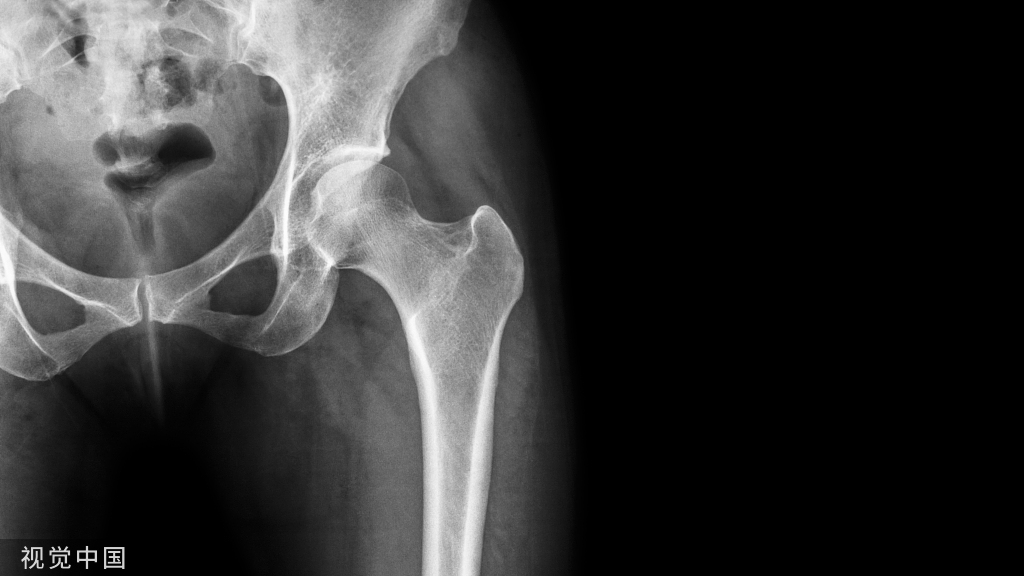

雌激素缺乏是原发性骨质疏松症重要的发病机制之一。雌激素水平降低会减弱对破骨细胞的抑制作用,破骨细胞的数量增加、凋亡减少、寿命延长,导致骨吸收功能增强。尽管成骨细胞介导的骨形成亦有增加,但不足以代偿过度骨吸收,骨重建活跃和失衡致使小梁骨变细或断裂,皮质骨孔隙度增加,导致骨强度下降。雌激素减少能降低骨骼对力学刺激的敏感性,使骨骼呈现类似于废用性骨丢失的病理变化。